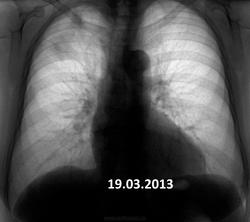

Пожилая опрятная женщина, жалоб нет, просит "отпустить". В феврале фтизиатры написали пневмонию. Сжалился - написал что-то вроде плеврофибрознотакая-то хрень.

Коли фтизиатры отпустили так на них и грех.Сопоставляя с архивом от туберкулёза не отмахнёшся.

Но ведь не может туберкулез меделенно развиваться 4 года?

имеет место. Томографировать надо обязательно.

Не надо сбрасывать со счетов и левую верхушку.

Очень даже может.

Увы! Мне кажется - справа имеет место рецидив. Валентин Львович не зря на левую верхушку обратил внимание.

На первом месте- Tbc.

На втором: Если в легком неясная картина - ищи БАР.

В любом случае ТМГ.

+1. Не пневмония это точно. Прогресс слишком долгий. Больше склоняюсь к онко.

Я за онкологию